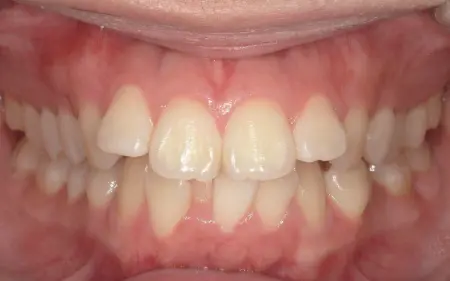

2025.12.2710代女性 突出感のある口元と乱れた歯並びをワイヤー矯正で改善した症例